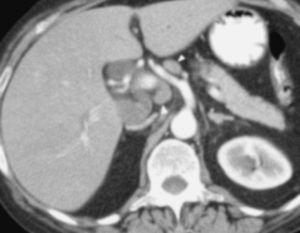

La TC helicoidal permitió, además, llevar a cabo un estudio detallado de los pequeños vasos arteriales y venosos peripancreáticos24-26 (fig. 2), mostrando mejores resultados que la angiografía por sustracción digital en el diagnóstico de la invasión vascular por cáncer de páncreas27. La valoración de estas pequeñas estructuras vasculares mejora el rendimiento de la TC en la estadificación tumoral28,29. La posibilidad de reconstruir en diferentes planos del espacio las imágenes axiales obtenidas ha sido evaluada por algunos autores30,31, obteniendo un mayor rendimiento de la TC para determinar la invasión vascular, fundamentalmente venosa, cuando las secciones transversas se interpretan en combinación con las reconstrucciones multiplanares que cuando se interpretan únicamente las secciones transversas (92-96% frente a 69-70%) (fig. 3).

Fig. 2.--Estudio de tomografía computarizada con contraste endovenoso en fase pancreatográfica en un paciente con neoplasia del cuerpo pancreático. Múltiples vasos mesentéricos dilatados secundarios a la infiltración venosa portomesentérica tumoral (flechas).